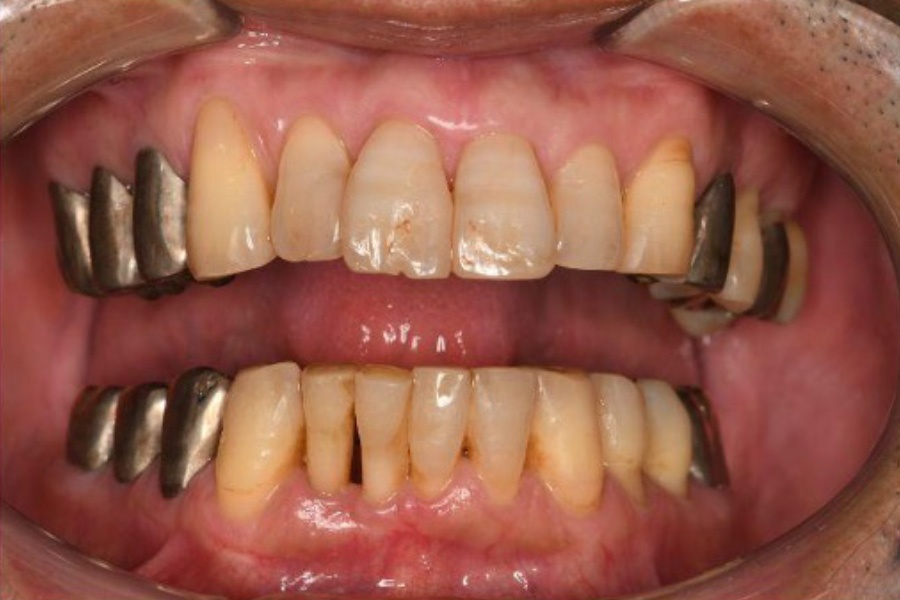

治療前

| 治療内容 | 全顎治療:歯周病治療、抜歯、根管治療、 咬合治療・矯正治療、フルメタルクラウン(保険) |